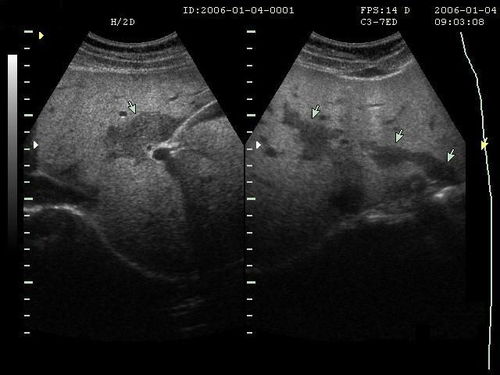

病情分析:您好:乙肝B超檢查安全,快速,無損傷,所以這成為很多乙肝患者復(fù)查要做的項(xiàng)目.意見建議:首先,乙肝B超檢查前要空腹,并做好檢查前的腸道準(zhǔn)備.腹腔的肝,膽,胰的B超檢查應(yīng)該不要吃東西,避免胃腸食物和氣體對(duì)超聲波的干擾,保證膽囊及膽管等器官內(nèi)有足夠的膽汁充盈,從而確保診斷的準(zhǔn)確性.乙肝B超檢查通常安排在每天上午.乙肝患者最好在做乙肝B超檢查前3日禁食牛奶,豆制品,糖類等易于發(fā)酵產(chǎn)氣食物,檢查前1天晚吃清淡少渣飲食,食后禁食一夜,注意休息,檢查當(dāng)天需早上需要空腹禁食,禁水.另外有些乙肝患者雖然沒有吃早餐,但在凌晨兩三時(shí)吃過東西,同樣會(huì)影響乙肝B超檢查效果.其次,乙肝B超檢查中一定要按照醫(yī)生要求,積極配合.在乙肝B超檢查中,醫(yī)生常常會(huì)要求乙肝患者一直“吸氣”,此時(shí)應(yīng)該按照醫(yī)生的指令進(jìn)行呼吸運(yùn)動(dòng),這樣才能有助于更好地觀察.此時(shí)“吸氣”可以促使肺部氣體充滿,這樣會(huì)使得膈肌向下移動(dòng),這樣乙肝B超檢查結(jié)果才能更好地顯示肝臟,膽囊.。